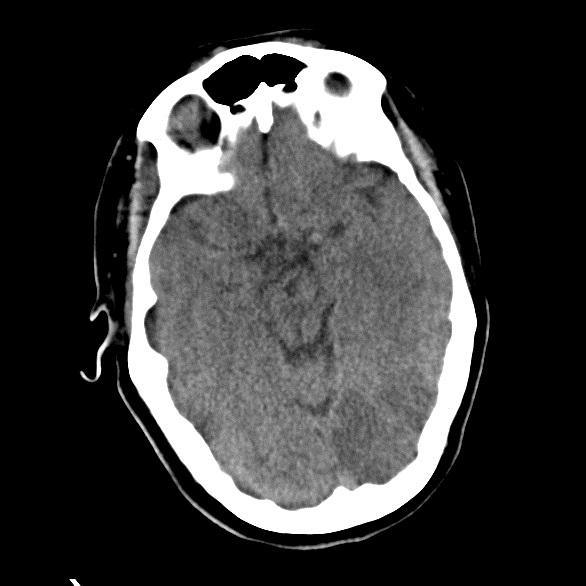

PCA Infarct